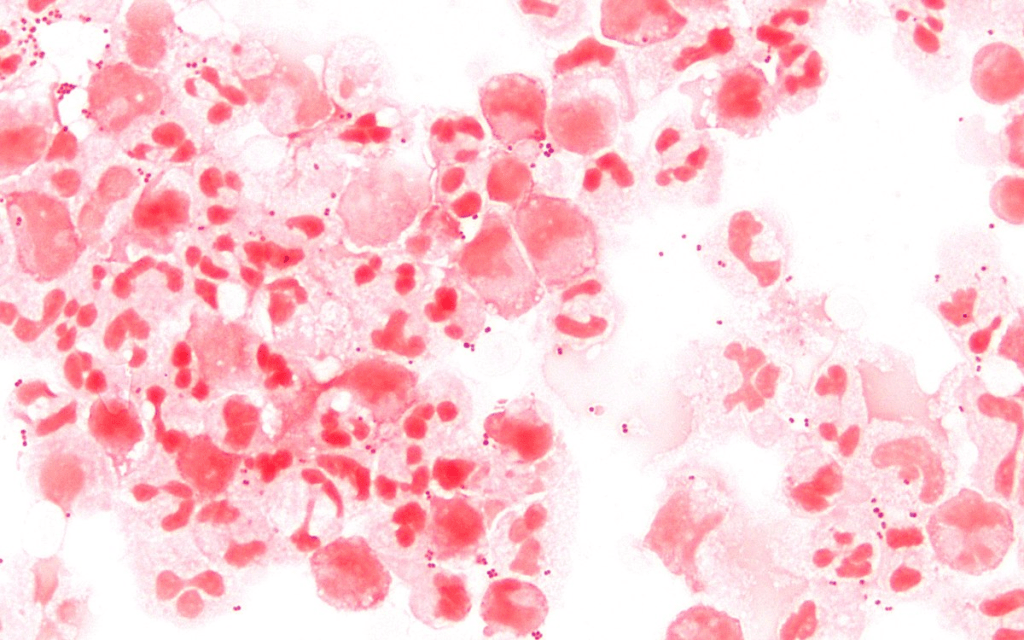

Neisseria meningitidis es el nombre de la bacteria que identificaron en el cuerpo del joven, causante de todos sus malestares. Misma bacteria que originó una infección, la cual, causó un shock séptico y un fallo multiorgánico. También, mientras se trataba de estabilizar, sufrió varias complicaciones, entre ellas la necrosis de brazos y piernas, además de la gangrena. Esta última fue la razón principal y última por la cual se tomó la decisión de amputarle los 10 dedos de las manos junto con ambas piernas por debajo de la rodilla.